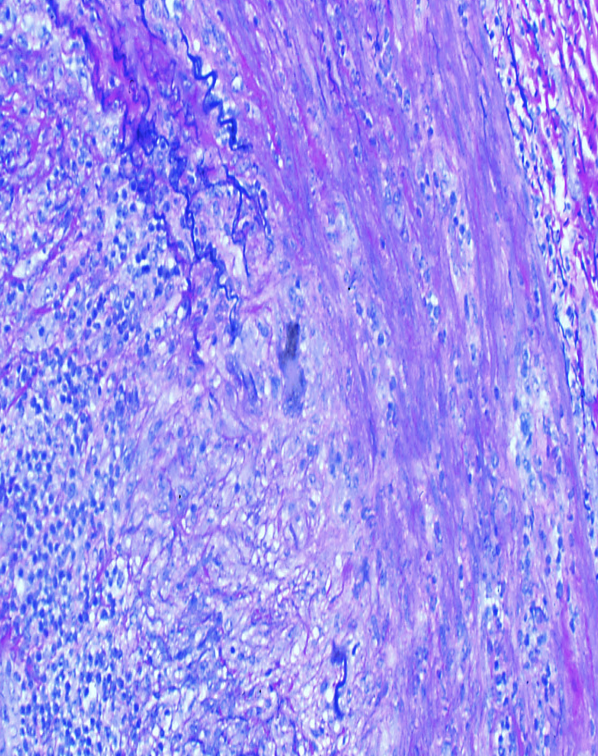

Fragmentation of elastic lamina associated with giant cell arteritis

Giant cell arteritis